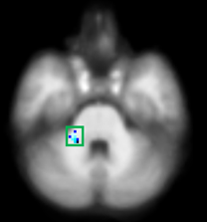

수면무호흡증에 따른 뇌구조 변화

| ▲지속군 |

호전군에서는 시각기억 경로의 회복(노란색)을 확인했으며, 발생군과 지속군에서는 시각기억 관련된 부위의 뇌손상(파란색을) 확인할 수 있다.